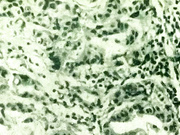

Описание: Грудь – одна из важнейших частей женского организма. И от ее здоровья во многом зависит самочувствие женщины. Как сберечь это здоровье? Какие меры предпринимать, чтоб не допустить заболеваний груди, вы узнаете, посмотрев видео. Одной из серьезнейших заболеваний груди является рак молочной железы. Это злокачественная опухоль из железистой ткани. Пик заболевания приходит на возраст 40-55 лет. В мире – это самая распространенная форма рака среди женщин. Факторы риска заболевания: отсутствие в анамнезе беременности, родов и периода грудного вскармливания, отягощенный семейный анамнез онкозаболеваний у кровных родственников, поздняя менопауза, травма груди в анамнезе, непрерывное употребление экзогенных гормонов с целью контрацепции в течении 10 лет. Симптомы рака молочной железы на ранних строках могут отсутствовать. Причиной для беспокойства должны стать уплотнения в груди, выделения из соска любого характера, если в это период вы не кормите ребенка грудью, эрозии, корочки, чешуйки в области соска, беспричинная деформация и втянутость соска, увеличение или уменьшение размеров грудь, увеличение или уменьшение подмышечных, подключичных и подлопаточных лимфоузлов. Несмотря на сложность заболевания, сегодня в мире разработано много методик органосохранных операций. Об этом и многих других способах лечения рассказывает эксперт в данной области.